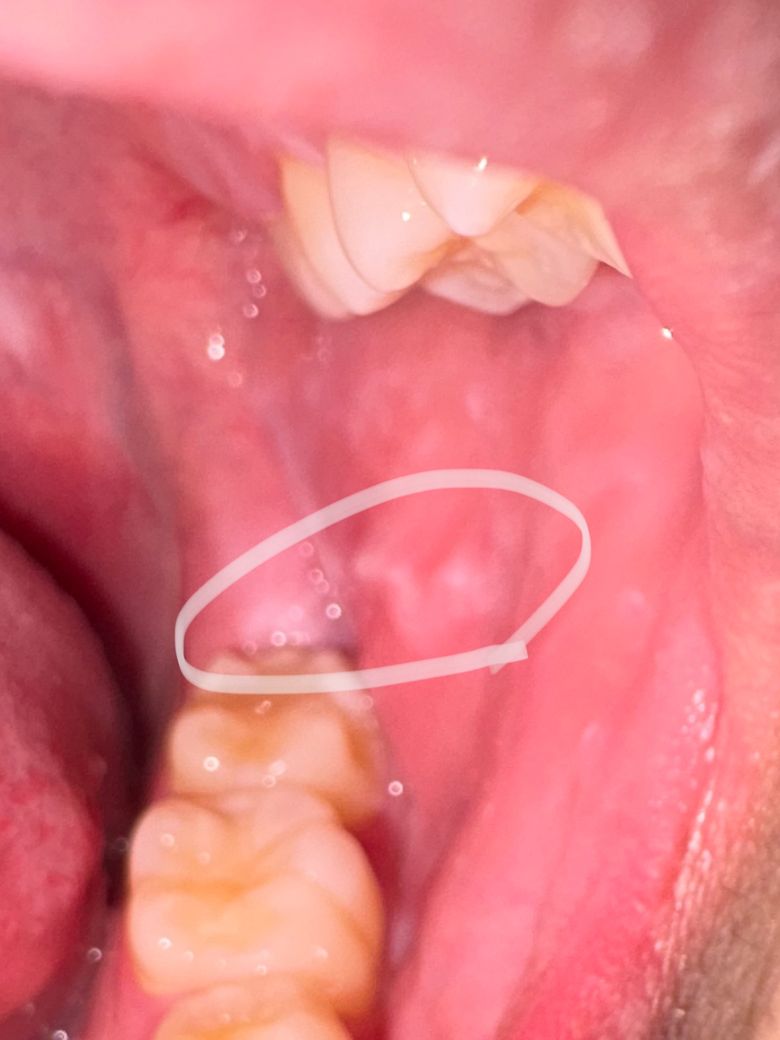

입 안 쪽이 하얗게 변했는데 뭘까요 ㅠㅠ

입 벽쪽이 하얗게 변했고 혀로 만지면 이로 잘못 깨물고 나서처럼 울퉁불퉁한 게 느껴집니다 가끔 얇은 껍질처럼 떨어지기도 해요 왜 그런 걸까요

해당 부분은 볼쪽의 살을 씹으면서 생기는 것으로 굳이 치료를 하지는 않으셔도 상관없습니다.

아래잇몸이 위쪽 치아에 자극을 받아서 생긴 자국같습니다. 사랑니 때문에 그럴수도 잇으니 치과에 가셔서 체크를 받아보세요.

현재 구내염이 생긴 것으로 보이며, 소독용 헥사메딘 가글액으로 가글을 하여 우선 관리하고 만약 해당부위에 통증 및 고름 악취가 나는 경우에는 치과 진료를 권합니다.

1. 깨물고 나서부터 그렇다면 단순 외상성 궤양일 수 있으나 사진상 양상은 그렇지는 않습니다.

2. 의심되는 병변으로는 편평태선이 있습니다.

3. 얇게 흰색 껍질처럼 떨어지는 것은 죽은상피세포(각질)라고 보시면 됩니다.

4. 구강내과가면 정확히 진단 받으실 수 있습니다.